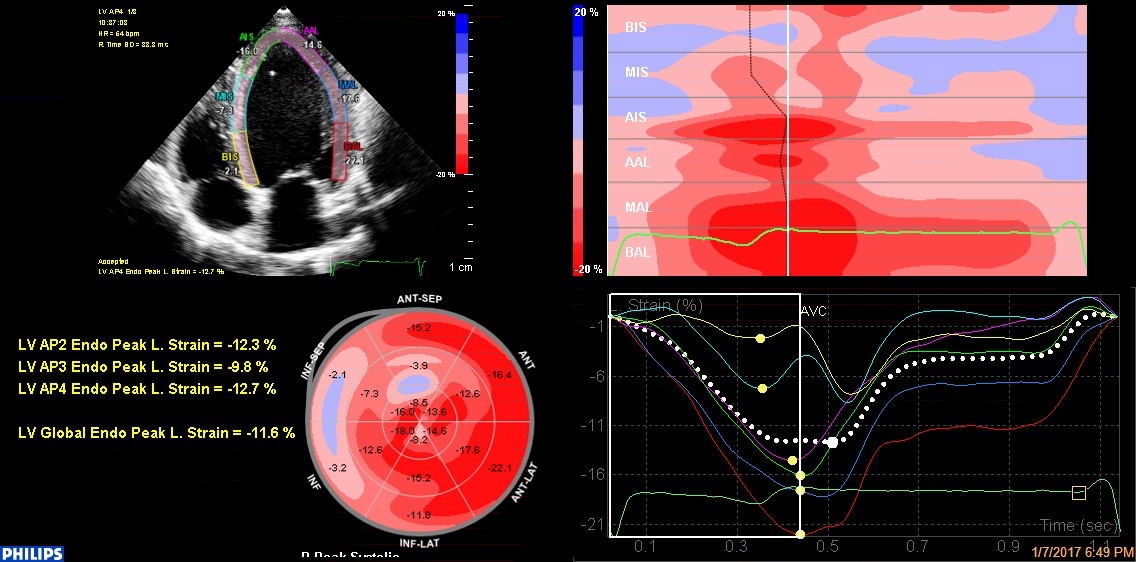

HeartModelA.I.

HeartModelA.I.は、日常の心エコー検査に、高度に自動化された定量化、3D表示、高い再現性をもたらします。

アナトミカルインテリジェンス

アナトミカルインテリジェンスにより、検査をより簡単に実施でき、再現性を高めることができます。